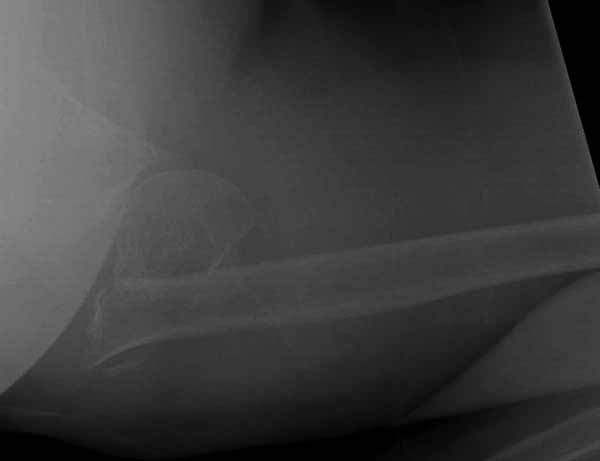

Набор мелких снимков не отражает истинную картину суставной поверхности лопатки, а также качество репозиции головки плеча. Необходимо доказать аксиальным снимком наличие покрытия головки. Правильная маркировка на рентген снимках и соответствие с выставленным диагнозом гарантирует от ошибок со стороной во время операции!

Здесь результат похожего случая, больная 87 лет, отягощенная сердечными делами и два года назад установка pacemaker и нескольких стентов. На третий день, сегодня утром сделали операцию. Послеоперационный псевдовывих связанный с релаксацией мышц и общим обезболиванием.